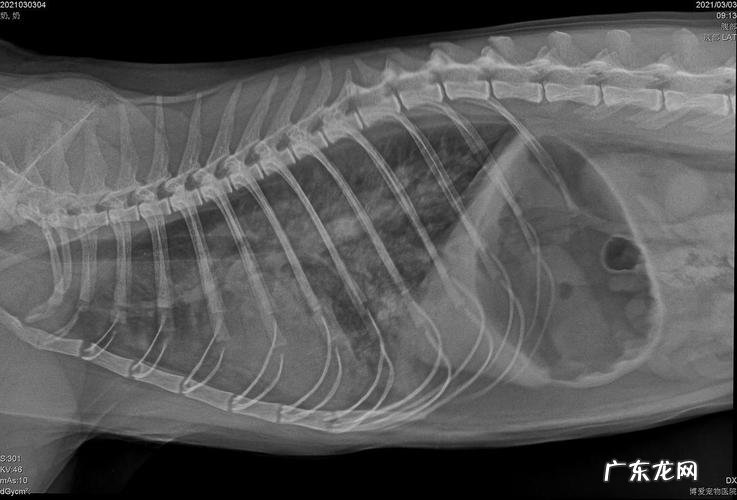

猫咪肺水肿能治好吗?猫咪肺水肿是一种严重的疾病 , 也属于比较难治疗的疾病 。猫咪肺水肿的治疗方法有很多 , 但一定要及时的治疗 。

不过 , 对于小猫来说 , 呼吸困难的症状可能没有那么明显 。因此 , 主人也不用过于担心 。一般 , 猫咪肺水肿的症状 , 在一周左右就会消失 。不过 , 对于年纪比较大些的猫咪 , 主人还是需要给它定期进行检查 , 看看猫咪是否有肺病 。当发现猫咪肺部出现异常时 , 主人也应该带着猫咪及时去宠物医院检查 。而且在检查结束后要注意及时更换猫粮等营养品 , 以免病情加重 。